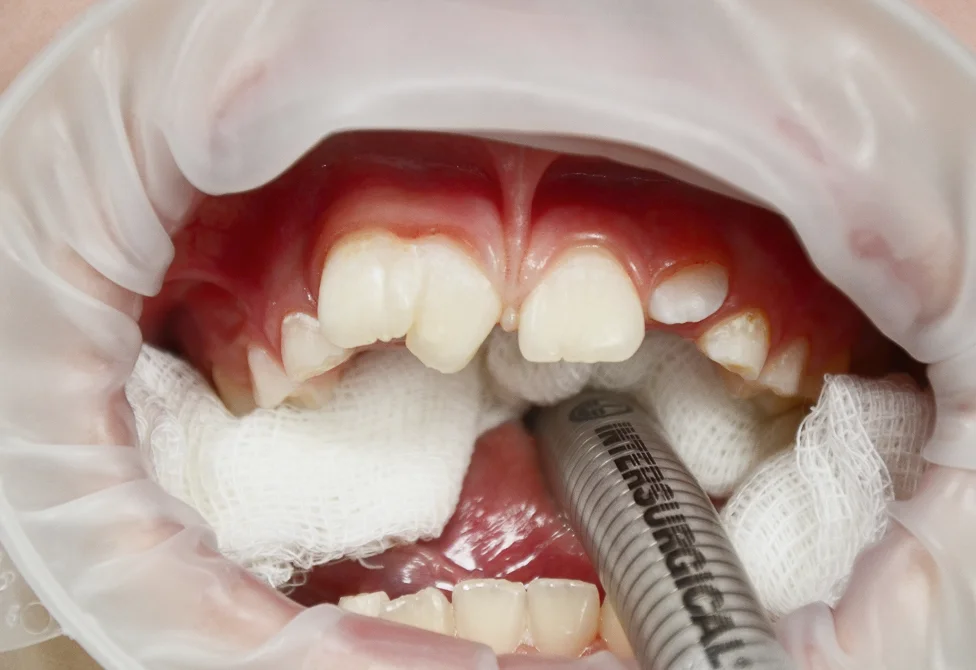

Пороки развития зубов встречаются в практике детского стоматолога гораздо чаще, чем кажется. Но одни и те же дефекты могут иметь разную природу, а лечение требует междисциплинарного подхода. Этот семинар систематизирует знания о пороках развития зубов и помогает выстроить

понятную клиническую логику диагностики и лечения.

Дифференцировать флюороз, молярно-резцовую гипоминерализацию (MIH) и несовершенный амелогенез — с пониманием природы каждого состояния и его границ.

Диагностировать dens invaginatus и выбрать тактику эндодонтического лечения в зависимости от степени инвагинации.

Классифицировать случай и принять обоснованное клиническое решение до начала лечения.

Олигодентия, сверхкомплектные зубы, шиловидные резцы, геминация — клиническая логика для каждого состояния.

Механизм формирования инвагинации. Клинические проявления и рентгенологическая картина. Риски осложнений и алгоритм принятия решения о лечении. Особенности эндодонтического лечения при разных степенях инвагинации.

Пороки твёрдых тканей: дифференциальная диагностика

Молярно-резцовая гипоминерализация (MIH), флюороз, несовершенный амелогенез, дисплазии дентина — клинические признаки каждого состояния и границы между ними. Классификация Wuerzburg 2.0. Дисплазии дентина: от облитерации пульповой камеры до «зубов-призраков».